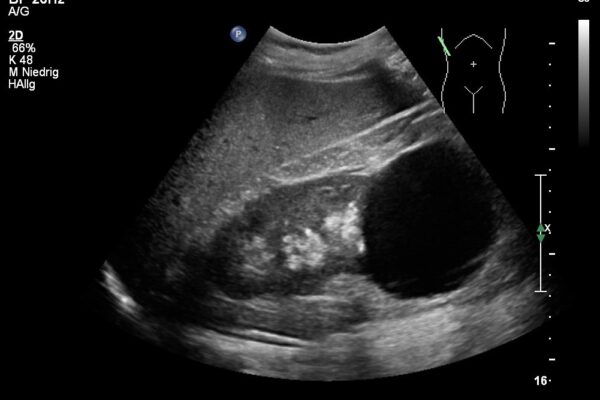

Eine Gewebe- oder Zellentnahme ist je nach Körperregion unter Ultraschallkontrolle gut durchführbar. Um Gewebematerial zu gewinnen, wird eine feine Nadel nach örtlicher Betäubung in den Krankheitsherd eingeführt und Flüssigkeit oder Zellen für die mikroskopische Untersuchung gewonnen. Am Ultraschallbildschirm kann die präzise Führung der Nadel verfolgt werden. Der Stich der Betäubung oder der Stich zur Biopsie sind meistens nur wenig schmerzhaft. Die gewonnenen Zellen oder die aspirierte Flüssigkeit werden dann durch einen Facharzt der Pathologie beurteilt.